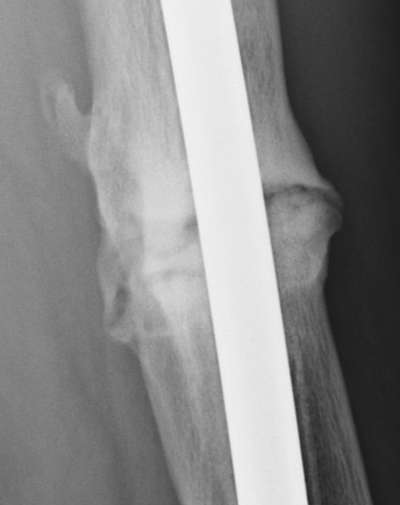

Jan. 31, 2006 Aug. 17, 2006 Apr. 17, 2007 Feb. 21, 2008